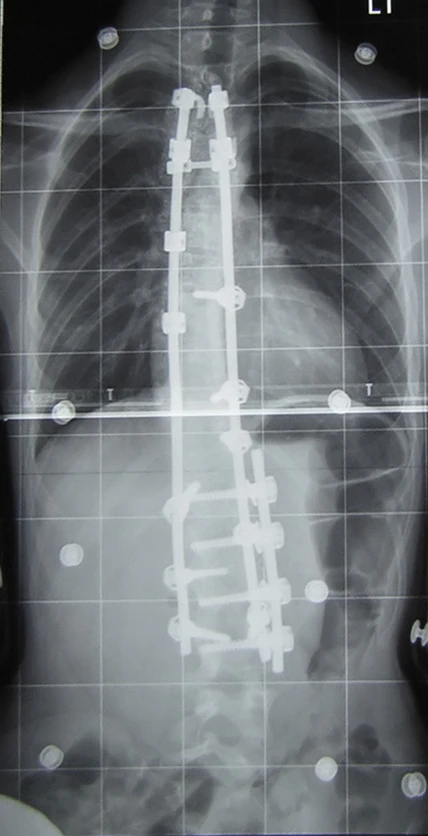

При оперативном лечении искривлённая часть позвоночника выпрямляется до определённого возможного угла при помощи металлических стержней и шурупов (т. н. педикулярных винтов), что ведёт к обездвиживанию этих отделов позвоночника. Операция при сколиозе подходит прежде всего для сильных искривлений, которые больше не могут лечиться другими методами. Оперативная фиксация может предотвратить дальнейшую прогрессию и ухудшение состояния.

Оптимальный возраст для исправляющих деформацию операций начинается с 13-15 лет, с окончанием основного скачка роста. В противном случае, за счёт активного роста костей пациента исправляющие фиксирующие системы могут привести к нежелательным последствиям, т.н. краншафтфеномену, т.е. выламыванию крепежа конструкции из костей растущего позвоночника из-за эффекта коленвала.

Оперативный разрез при заднем доступе находится на средней линии туловища и одном из крыльев тазовой кости. Используются различные системы металлических стержней, которые крючками или шурупами (т. н. педикулярными винтами) прикрепляются к позвоночнику и затем изменяют его кривизну на больших участках. Для лучшей стабилизации всей конструкции стержни имеют поперечные соединения (мостики).

После операции теряется подвижность в зафиксированных отделах позвоночника. Это способствует впоследствии сращению тел позвонков в единый костный блок необходимой длины и желаемой геометрии. Недостаток метода состоит в том, что позвоночник на больших участках оказывается обездвижен, и общая подвижность позвоночного аппарата ограничена, что вынуждает пациента менять привычные стереотипы движений.

Результаты операций с передним доступом выглядят лучше в косметическом плане и функционально предпочтительнее. Операция с заднего доступа сегодня обычно не требует заключительного ношения корсета, но без дополнительной резекции реберного горба её результаты в косметическом плане недостаточны.